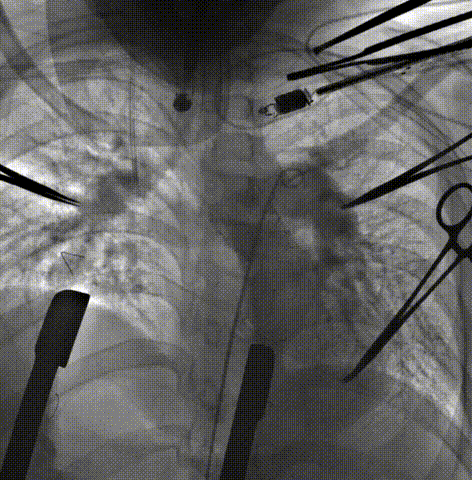

患者男性,11岁,因先天性肺动脉闭锁行带瓣补片右室流出道重建术后11年,近期症状加重,心脏超声提示肺动脉瓣重度返流。术前行详细影像学重建与评估及多学科讨论手术策略。影像学重建显示患者肺动脉较短,截面呈椭圆形,腰部径宽16-32mm,形态测算介入瓣植入后直径22mm。手术经胸小切口入路,通过食道超声定位,经右室流出道穿刺植入22号Salus介入瓣。由于此前应用带瓣补片重建的主肺动脉质地较硬,主肺动脉截面形状较扁呈椭圆而非正圆形,介入瓣释放后支架四周难以与主肺动脉内壁完全贴合,食道超声提示主肺动脉右侧存在少量瓣周漏。继而行环缩部分主肺动脉。再次行经食道超声及肺动脉造影显示介入瓣植入位置理想,无瓣周漏及中央返流。

病例1 CT重建肺动脉

病例1 右室流出道截面呈椭圆形